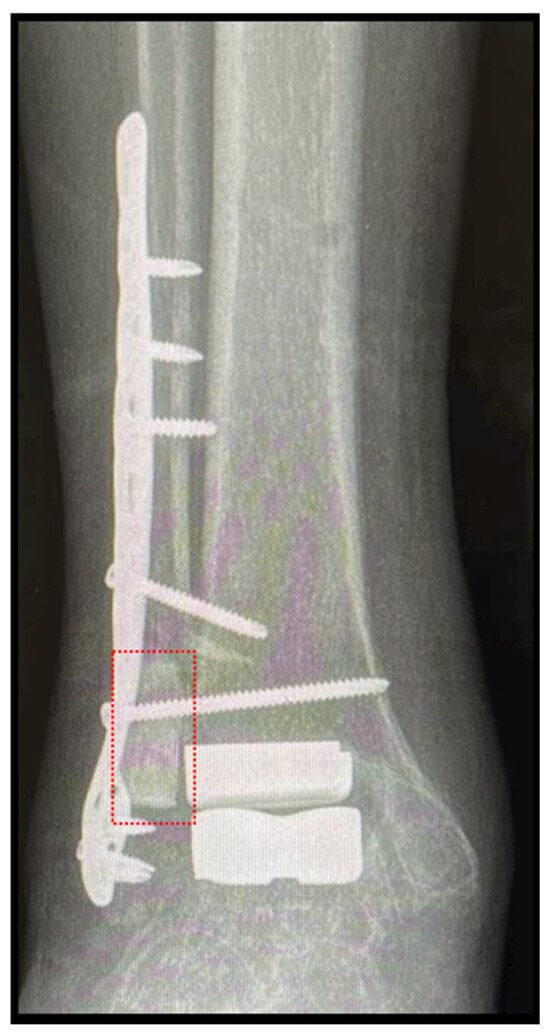

Figure 4.

Total ankle replacement through lateral approach in a case of ankle ankylosis. Note: application of the b.Bone™ prism (box in red) to fill the bone gap occurred during the transfibular approach. Follow-up at 4 months.